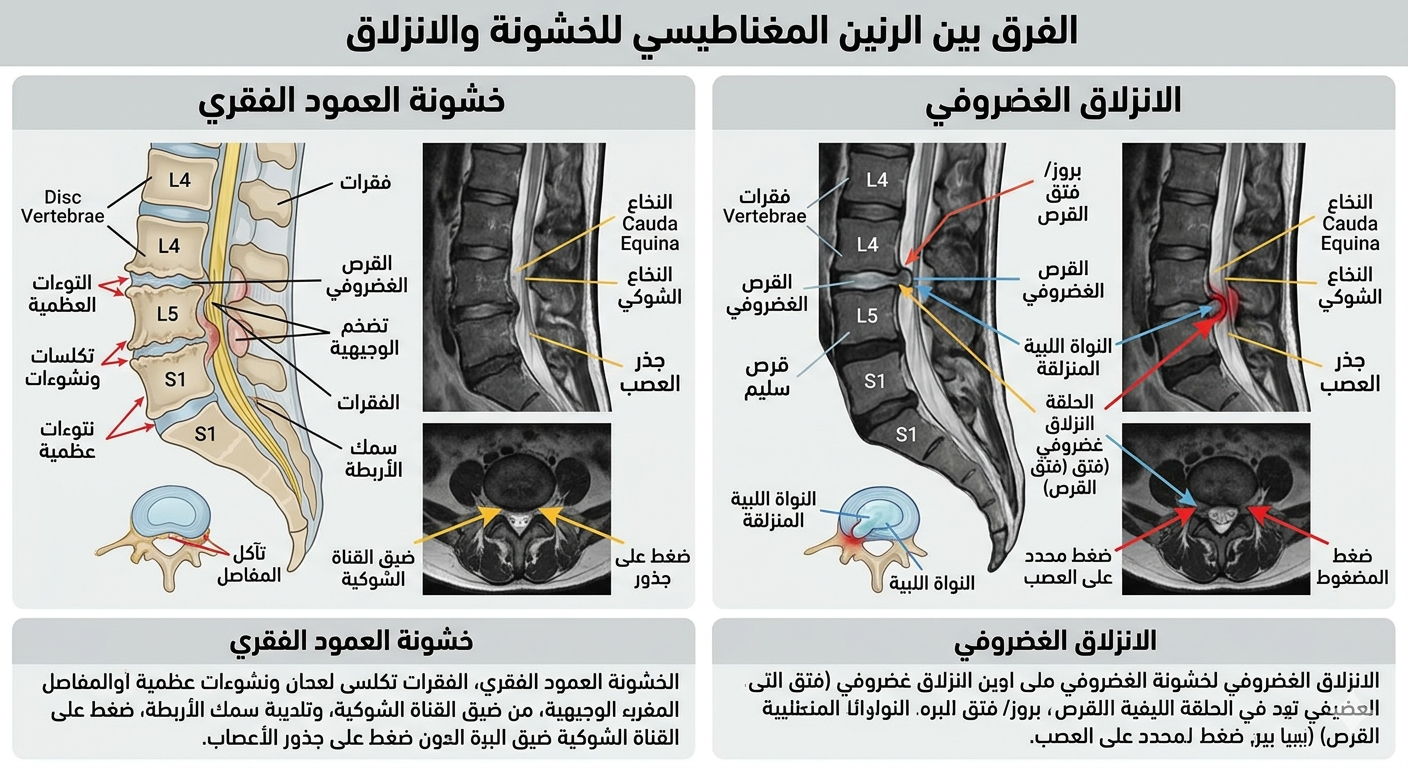

الفرق بين خشونة الفقرات والانزلاق الغضروفي

يكمن الفرق بين خشونة الفقرات والانزلاق الغضروفي في طبيعة المشكلة نفسها؛ فالخشونة ترتبط بتغيرات مزمنة تحدث ببطء مع التقدم في العمر أو الإجهاد المستمر، بينما يحدث الانزلاق الغضروفي عندما يبرز جزء من الغضروف و يضغط على الأعصاب بشكل مباشر. كما أن الفرق بين الانزلاق الغضروفي وانزلاق الفقرات مهم أيضًا، لأن انزلاق الفقرات يعني تحرك فقرة من مكانها الطبيعي، وهو يختلف عن مشكلة الغضروف من حيث السبب والعلاج.

الأشعة السينية والرنين المغناطيسي

تعد الأشعة السينية من الفحوصات المهمة في تشخيص خشونة الرقبة، لأنها تظهر ضيق المسافات بين الفقرات أو وجود نتوءات عظمية. أما الرنين المغناطيسي، فهو الأدق لتوضيح شكل غضروف الرقبة، حيث يكشف مكان الانزلاق الغضروفي، ودرجة الضغط على الأعصاب أو الحبل الشوكي، مما يساعد على تحديد خطة العلاج المناسبة.